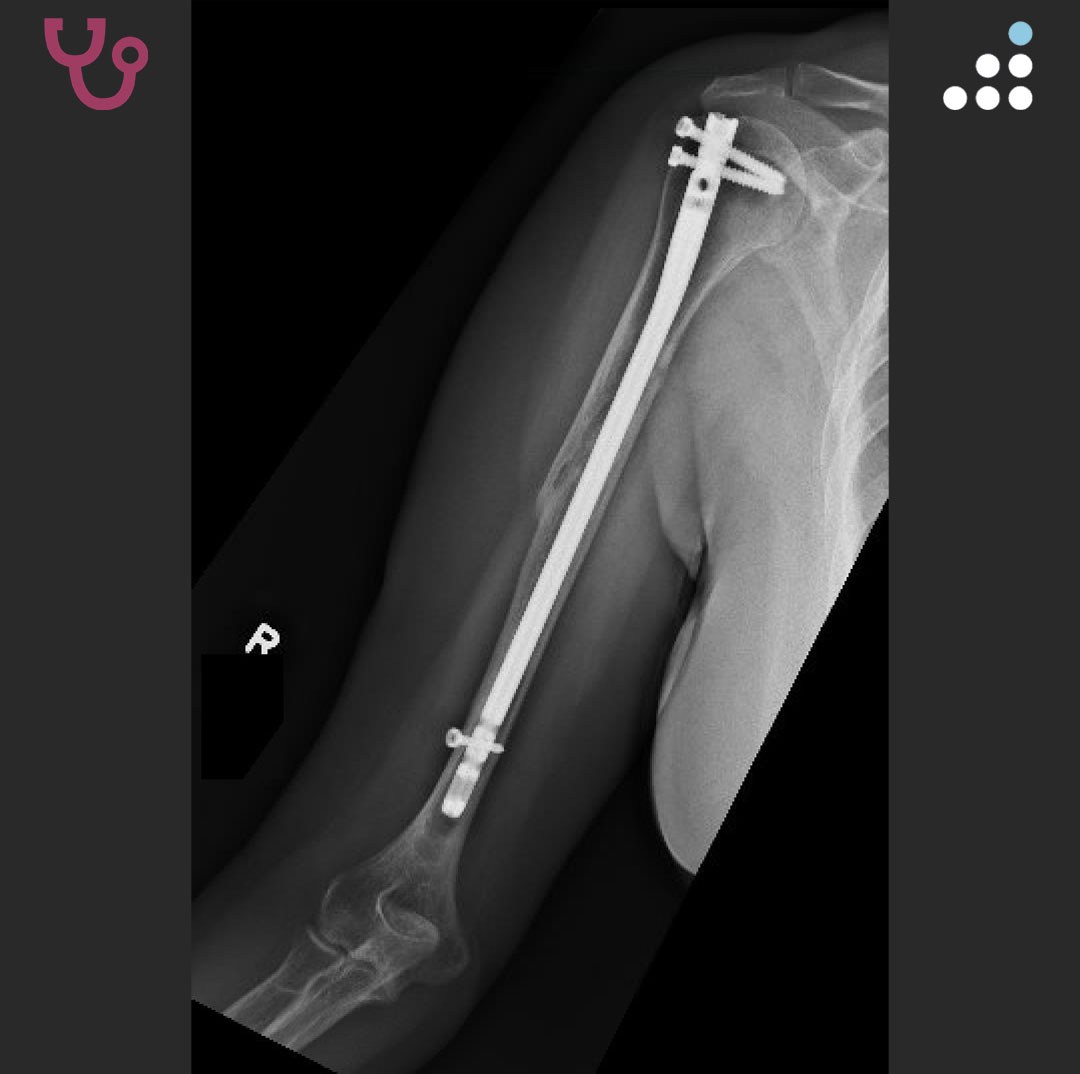

Here is a new case by Dr. Richard Yoon (@yoon_rs) and @RWJBarnabas Health. HUMERAL SHAFT NONUNION S/P IMN IN A 54F This case is sponsored by the @FOTNorthAmerica Lower Extremity Dissection Course and 16th Annual Meeting in Las Vegas, NV, Jan 29-30, 2026. How would you manage